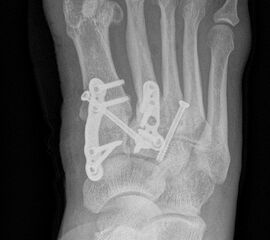

Die Korrektur des Spreizfußes und die Stabilisierung des TMT I ist das zentrale Element zur Entlastung des TMT II und III Gelenks. Dadurch kann die Lastachse wieder auf den ersten Strahl geführt werden. Aus Gründen der Stabilität sollte die Indikation zu einer Lapidusarthrodese großzügig gestellt werden. Eine TMT II und ggf. TMT III Arthrodese wird dann unter Berücksichtigung des Metatarsalindex unter Längenerhalt oder leichter Kürzung durchgeführt. Beim Pes metatarsus adductus kann der Eingriff mit einer Achskorrektur durchgeführt werden, um die Adduktionsstellung des Mittelfußes zu korrigieren (Abb. 9 und 10).

Zum Lesen der Bildbeschreibung und zur Vollansicht bitte die Bilder anklicken. Bilder: C. Hase

Es gibt neben der Möglichkeit mit der in situ TMT II, III Arthrodese auch die Möglichkeit Fehlstellungen wie den Pes metatarsus adductus zu adressieren (Abb. 9 und Abb. 24 zeigen das prä- und postoperative Röntgenbild eines Patienten mit Pes adductus Korrektur).

Zum Lesen der Bildbeschreibung und zur Vollansicht bitte die Bilder anklicken. Bilder: C. Hase.

• Temporäre Fixierung mit 1,6 K-Drähten, BV- Kontrolle. Bei korrekter Stellung definitive Osteosynthese entweder mit je 2 Kompressionsschrauben, Platten oder Klammern.

• Die mechanisch stabilste Situation ist mit dorsalen winkelstabilen Platten, optional mit Kompressionsschraube zu erreichen 3.

• BV-Kontrolle von Stellung der Knochen und der Lage des Osteosynthesematerials.

• Röntgenkontrolle nach 8-10 Wochen, dann - je nach knöchernem Durchbau - Übergang zur Vollbelastung im Konfektionsschuh (Abb. 24 und 25).